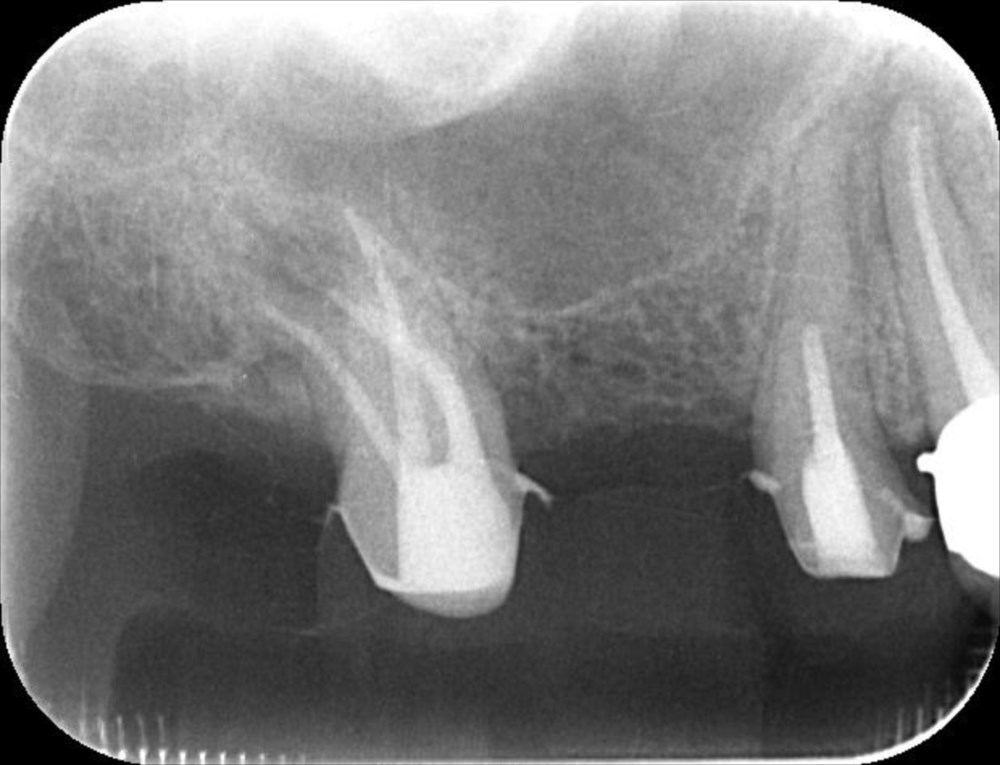

このような大きく曲がった根管を確実に治療します。とても難易度は高いですが、その分、患者さんと担当ドクターから感謝してもらえるので、やりがいがありますね😊